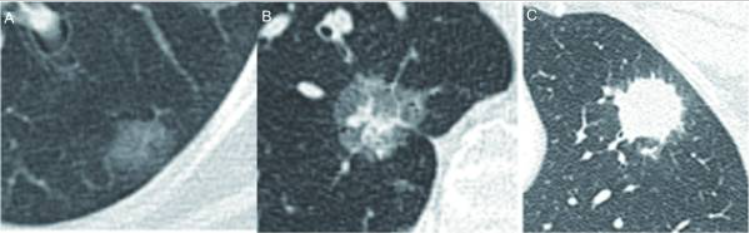

不同密度的肺结节,其恶性概率也不同,依据结节密度将肺结节分为三类:实性结节、部分实性结节和磨玻璃密度结节。其中,部分实性结节的恶性概率最高,随后则是磨玻璃密度结节和实性结节。

肺结节的密度分类。A(左):磨玻璃结节;B(中):部分实性结节;C(右):实性结节。图源:《中国肺部结节分类、诊断与治疗指南(2016年版)》